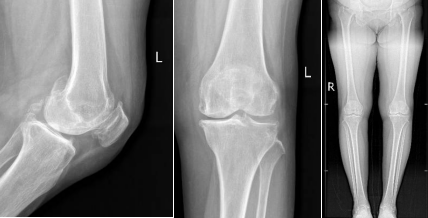

患者術前DR

術前機器人采集患者影像學數(shù)據(jù)進行手術規(guī)劃制定手術參數(shù)